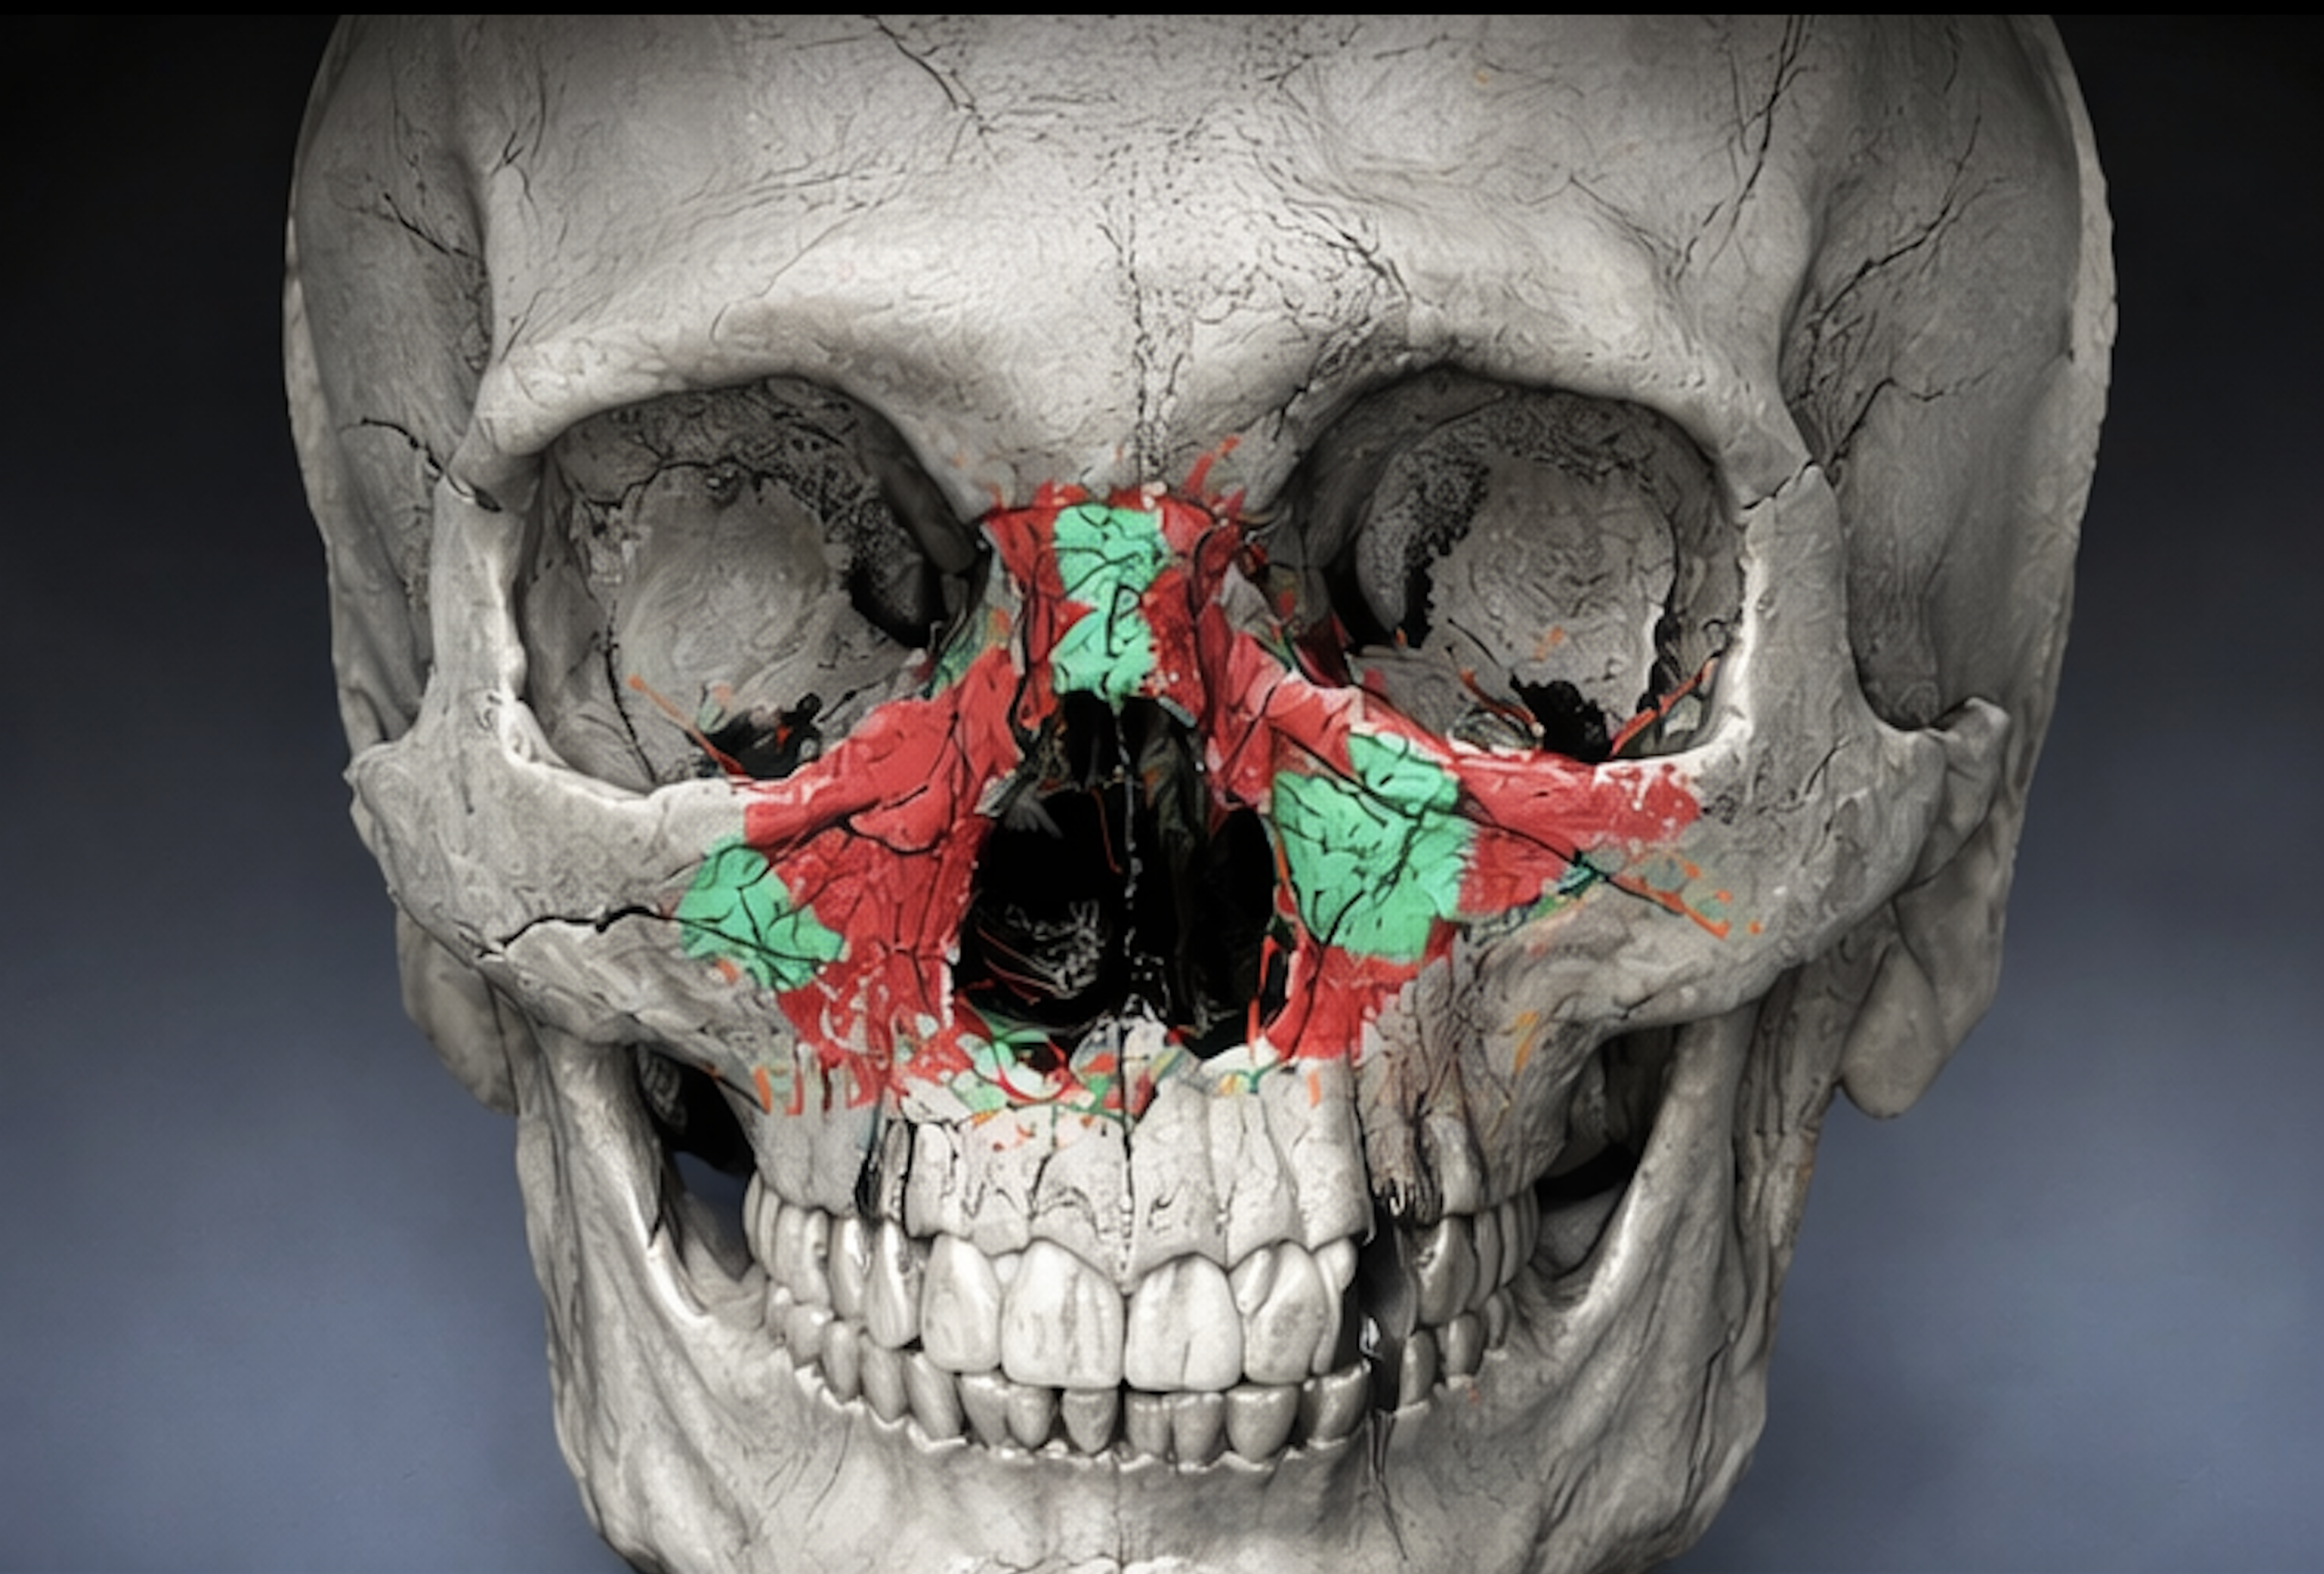

Trauma Case Report – Apr 22, 2025

Gunshot suicide and the interdisciplinary management of a complex craniofacial injury: A case report and review of literature

Yildirim A., Hertach R., and Yildirim V.

Suicide ranks among the causes of death in industrialized nations. The authors present a case demonstrating how a firearm-related suicide attempt can be effectively managed and how long-term quality of life may be significantly improved through appropriate medical and psychological intervention.